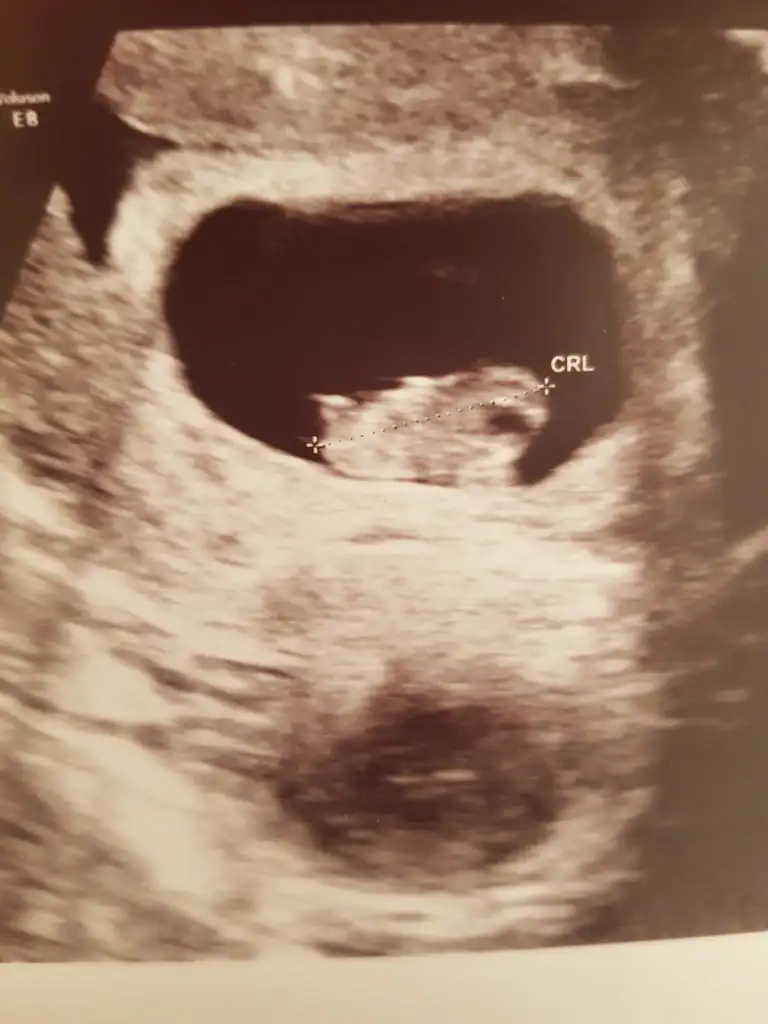

Yani cok eminim biri kiz biri erkek biri çıkıntılı biri cikintisiz öğrenince yazın merk ettim

Hadi hayırlısı inşallahYani cok eminim biri kiz biri erkek biri çıkıntılı biri cikintisiz öğrenince yazın merk ettim

Ams cnm şöyle bir şey daha var benim ultarsonda gördüğüm tek yumurta ikizi gibiydi kese birdi sanki eğer tekse cinsiyetleri de aynıdır çok belliydi tek yumurta ikizleri olduğuYani cok eminim biri kiz biri erkek biri çıkıntılı biri cikintisiz öğrenince yazın merk ettim

Kese cok farklıydı bilmiyorum bayan Tekmi dedi cıftmi biri cok çıkıntılı oglumunkide cok benziyotAms cnm şöyle bir şey daha var benim ultarsonda gördüğüm tek yumurta ikizi gibiydi kese birdi sanki eğer tekse cinsiyetleri de aynıdır çok belliydi tek yumurta ikizleri olduğu